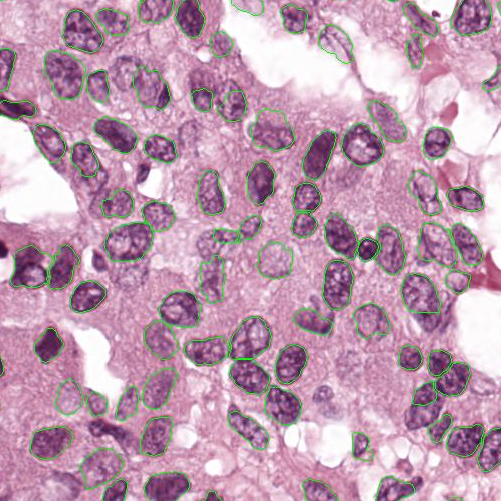

As an essential part of digital pathology, histopathology image analysis is playing increasingly important role in cancer diagnosis, which can provide direct and reliable evidence to diagnose the grade and type of cancer. This paper deals with nuclei segmentation, an important step in histopathological image analysis. The purpose of nuclei semgentation is not only counting the number of nuclei but also obtaining the detailed information of each nucleus. So unlike nuclei detection, here the outputs are the contour of each nucleus instead of only the position of their central points. Hence we can exactly extract each nucleus from the image and make it available for further analysis. For example, the features of the individual nucleus and the distribution of nuclei clusters can be used to grade and classify status of breast cancers [3, 4]. Because of appearance variation such as color, shape, and texture, nuclei segmentation from histopathological images could be very challenging, as illustrated in Fig.1, in which it is very challenging even for human to recognize and segment all nuclei within the images. Fig.1(a) and Fig.1(b) illustrate two histopathological images from different organs. Fig.1(c) and Fig.1(d) are two histopathological images from same organ but have different cancer grade.

Figure 1: (a)Colon cancer (b)Prostate cancer (c)Breast cancer (grade I) (d)Breast cancer(grade III)